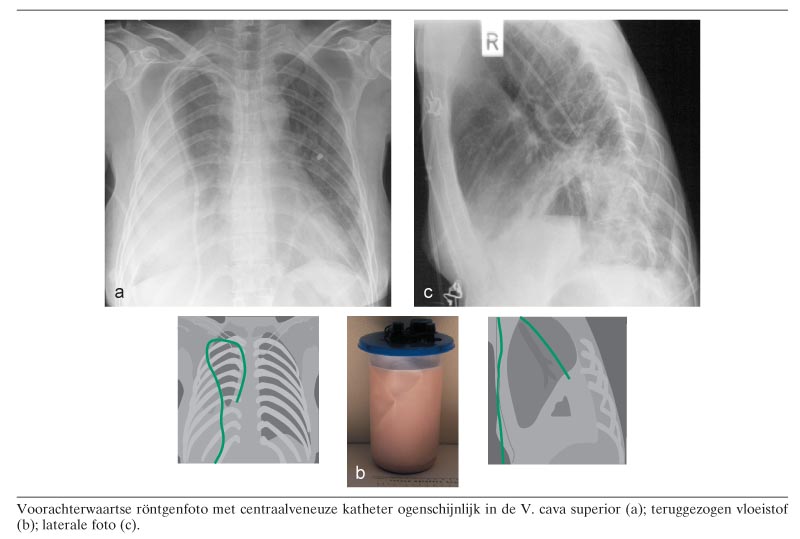

Een 41-jarige vrouw, sinds 8 jaar bekend wegens spinocerebellaire ataxie met chronische diarree en dysfagie ten gevolge van autonome disfunctie, kreeg een getunnelde centraalveneuze katheter via de V. subclavia dextra wegens falen van enterale voeding. Een controlethoraxfoto in voorachterwaartse richting toonde een zich normaal projecterende katheter met de punt in de V. cava superior. Vrijwel meteen nadat de totale parenterale voeding was begonnen kreeg patiënte toenemende pijn op de borst en werd zij progressief kortademig. Een nieuwe thoraxfoto toonde ophoping van pleuravocht lateraal in de rechter hemithorax en een ogenschijnlijk goede positie van de katheter (figuur a)…